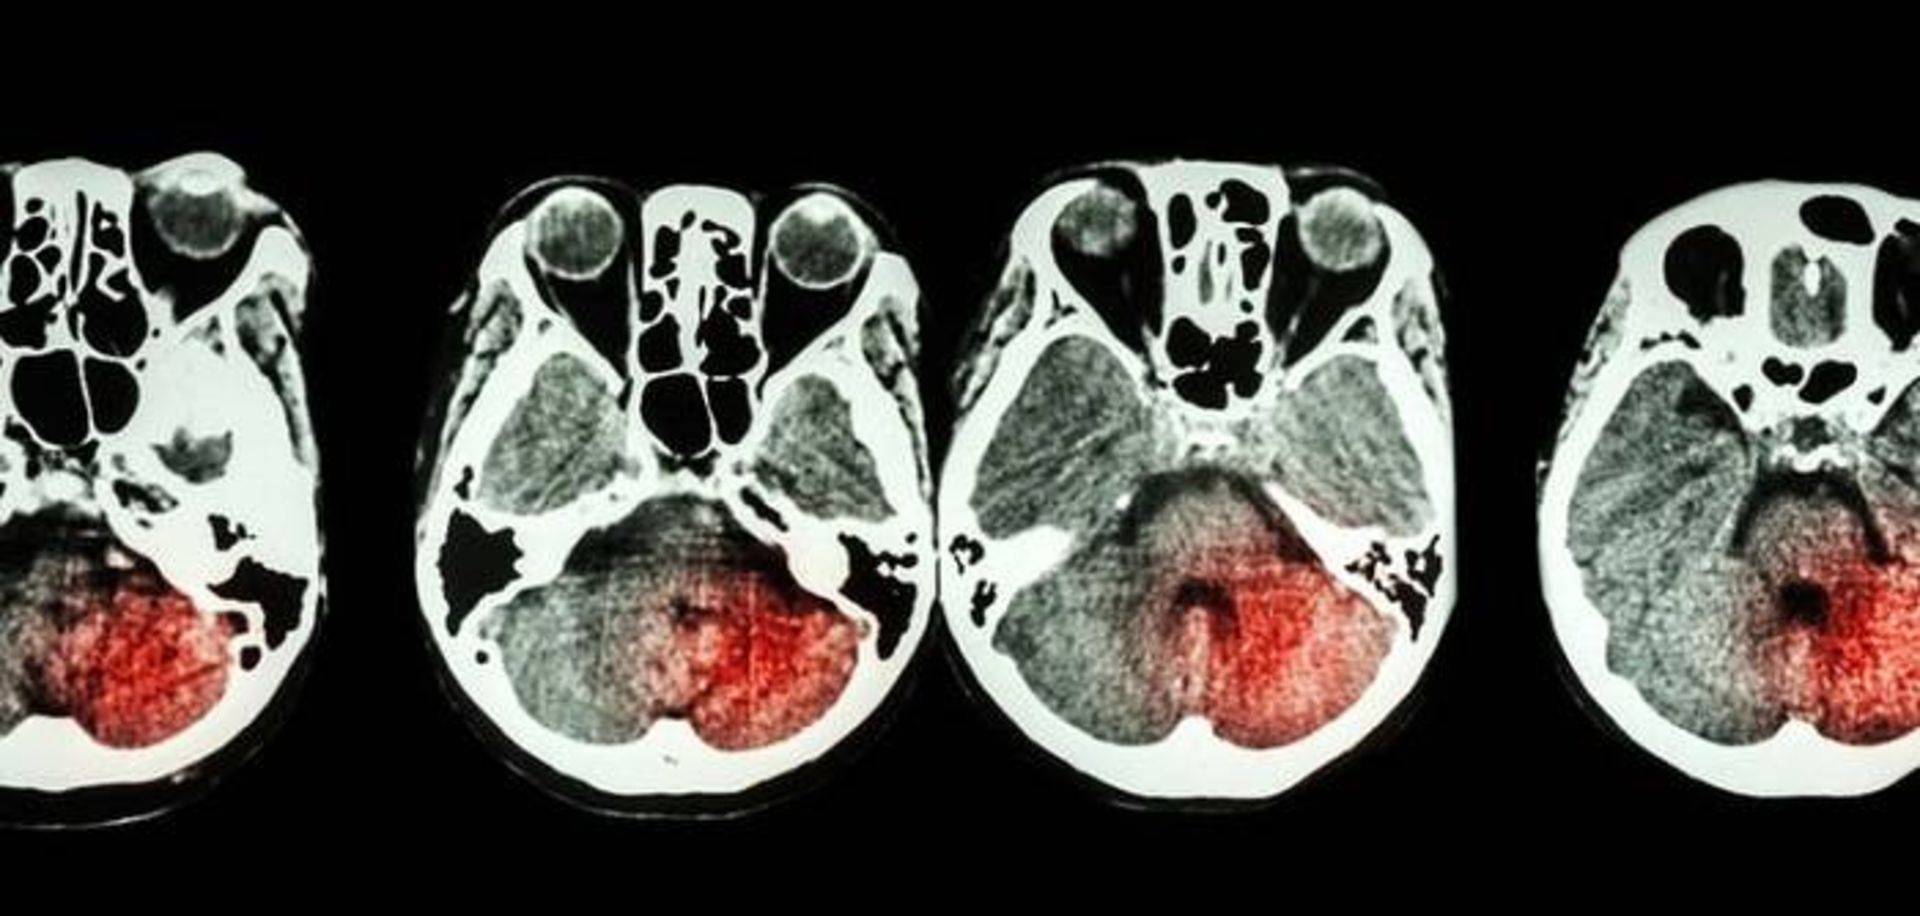

نتایج یک مطالعه‌ی بزرگ نشان می‌دهد رابطه‌ی غذاهای مختلف با سکته‌ی ایسکمیک و سکته‌ی هموراژیک یکسان نیست.

سکته‌ی ایسکمیک زمانی رخ می‌دهد که لخته‌ی خونی یکی از سرخرگ‌هایی که به مغز خون می‌رساند را مسدود کند یا در قسمت دیگری از بدن تشکیل شده و با گردش خون به مغز برسد و جریان خون بخشی از مغز را متوقف کند. سکته‌ی هموراژیک زمانی اتفاق می‌افتد که خونریزی در مغز وجود داشته باشد که به سلول‌های اطراف آسیب برساند. حدود ۸۵ درصد از سکته‌ها ایسکمیک و ۱۵ درصد از نوع هموراژیک هستند.